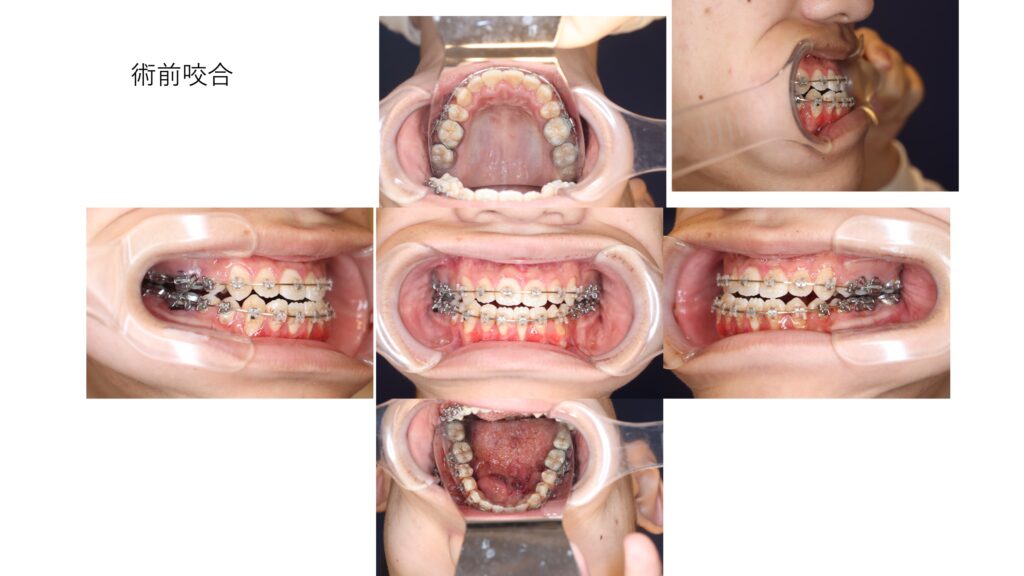

矯正治療開始前の口腔内の状態

舌のリンパ管腫は硬化療法の効果でよく縮小しています。臼歯早期接触を原因とする開咬が明らかです。

術前の顔貌写真と咬合を示します。

本格的な矯正治療が行われ、開咬は良好にコントロールされています。

しかし、下顎の前突は骨格性の要因が大きく、矯正治療のみでの改善には限界がありました。そのため、外科的治療が必須と判断しました。